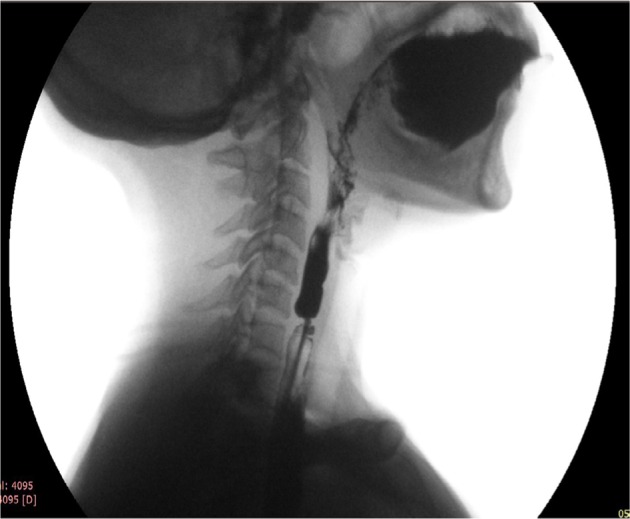

Forceful propulsion of barium through a relatively narrow opening of the web often produces a “jet phenomenon”. Width of the jet immediately below the level of the web indicates the degree of narrowing (Figure 3). Sometimes, the web cannot be seen and its possibility is considered only because the jet phenomenon is observed; though infrequent, presence of this sign is fairly diagnostic of a web.61 Its presence suggests a critical narrowing, and hence, patients with it are more likely to be symptomatic. In a recent prospective study, 86% of the esophageal webs were diagnosed by barium swallow and most of these webs showed jet phenomenon and poor lumen distensibility below the web.6

Figure 3.

Lateral view of barium swallow study in a patient with circumferential web with severe narrowing producing “jet phenomenon” below the level of narrowing because of the web.